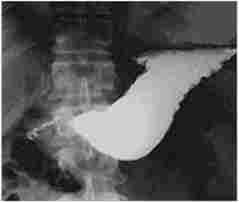

При стадіюванні стенозу ПДЗ особливе місце відводиться рентгеноконтрастність методу (рис. 12.5).

Мал. 125.

Рентгенологічна картина стенозу пілородуоденалиюй зони